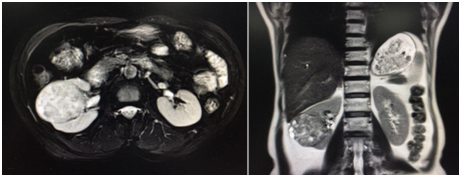

廣東的沈阿姨因為出現血尿,到醫院檢查發現右側腎臟上長了一個 5cm的大腫瘤。為了給她最好的醫療條件,家人多方打聽來到中國醫學科學院腫瘤醫院深圳醫院泌尿外科就診。

接着進來門診的是一名同行,來自深圳某醫院的小夏同樣因為檢查發現左腎一枚 6cm 的腫瘤,熟悉醫療領域的他,是慕名來到王東文教授的診室,評估病情後夏醫生也住進了泌尿外科病房。看着窗外鬱鬱蔥蔥的山景,夏醫生感慨:「深圳這麼多醫院,你們的專家和環境真是雙一流!」

沈阿姨、夏醫生入院後都完善了術前檢查。綜合腎臟腫瘤的位置、大小、深度及血管情況後,王東文教授給他們制定了 3D 腹腔鏡根治性腎切除手術方案。